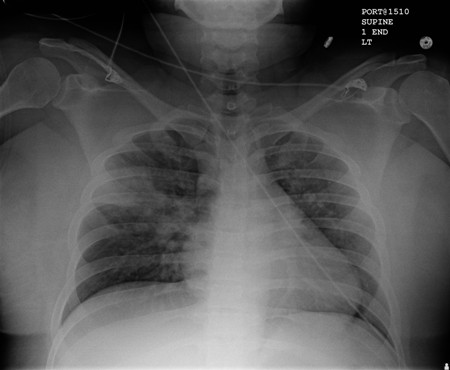

Chest x-ray

A chest x-ray should be obtained early in the evaluation of chronic cough.[38] Although it is not diagnostic of the most common causes, findings may quickly divert the evaluation to causes of greater gravity, such as structural lung diseases. These include lung cancer, pulmonary fibrosis, tuberculosis, bronchiectasis, pneumonia, aspiration, and sarcoidosis.[Figure caption and citation for the preceding image starts]: Chest x-ray showing hyperinflation in a patient with COPD. The hyperinflation is caused by the emphysema component of COPD, rather than the chronic bronchitis that underlies symptoms of coughFrom the personal collection of Dr M. A. Sharifabadand, SUNY at Stony Brook School of Medicine, Department of Pulmonary and Critical Care Medicine, Mineola, New York and Dr J. P. Parsons, The Ohio State University Medical Center, Columbus; used with permission [Citation ends].com.bmj.content.model.assessment.Caption@65a65855[Figure caption and citation for the preceding image starts]: Chest x-ray showing multiple miliary lung metastases (arrows). The primary tumour was a thyroid carcinomaE. Dick, Student BMJ. 2001;9:10-12 [Citation ends].com.bmj.content.model.assessment.Caption@25657fee[Figure caption and citation for the preceding image starts]: Chest x-ray showing left hilar carcinoma (arrow)From: E. Dick, Student BMJ. 2000;8:358-360 [Citation ends].com.bmj.content.model.assessment.Caption@567b9fef[Figure caption and citation for the preceding image starts]: Chest x-ray showing a cavitating right hilar carcinoma (arrow)E. Dick, Student BMJ. 2001;9:10-12 [Citation ends].com.bmj.content.model.assessment.Caption@3d6fa55[Figure caption and citation for the preceding image starts]: Chest x-ray in a patient with bronchogenic carcinoma showing a left-sided pleural effusionFrom: R. Thakkar, Student BMJ. 2001;9:458 [Citation ends].com.bmj.content.model.assessment.Caption@5b46acec[Figure caption and citation for the preceding image starts]: Chest x-ray showing interstitial fibrosis in a patient with amiodarone pulmonary toxicityFrom the personal collection of Dr A. Pataka and Professor P. Argyropoulou, Aristotle University, Thessaloniki, Greece; used with permission [Citation ends].com.bmj.content.model.assessment.Caption@2c3c94b0[Figure caption and citation for the preceding image starts]: Chest x-ray showing pulmonary tuberculosis with cavitationFrom the personal collection of Dr M. Narita, Department of Pulmonary and Critical Care Medicine, University of Washington [Citation ends].com.bmj.content.model.assessment.Caption@3dd7f84b[Figure caption and citation for the preceding image starts]: Chest x-ray showing multiple discrete nodules throughout both lungs (one of which is circled) in a patient with miliary tuberculosisE. Dick, Student BMJ. 2001;9:10-12 [Citation ends].com.bmj.content.model.assessment.Caption@23fa6365[Figure caption and citation for the preceding image starts]: Chest x-ray with lack of normal tapering producing a tram line in a patient with bronchiectasisFrom the personal collection of Dr S.M. Bhorade, University of Chicago Medical Center; used with permission [Citation ends].com.bmj.content.model.assessment.Caption@36b415f2[Figure caption and citation for the preceding image starts]: Chest x-ray with dilated and thickened airways in a patient with bronchiectasisFrom the personal collection of Dr S.M. Bhorade, University of Chicago Medical Center; used with permission [Citation ends].com.bmj.content.model.assessment.Caption@78e208fa[Figure caption and citation for the preceding image starts]: Chest x-ray showing increased opacification of the right perihilar region and superior segment of the right lower and upper lobes consistent with worsening aspiration pneumoniaFrom the personal collection of Dr R. Kanner, University of Utah School of Medicine [Citation ends].com.bmj.content.model.assessment.Caption@71be2c1f[Figure caption and citation for the preceding image starts]: Portable chest x-ray with bibasilar opacities, worse on the right than the left, in a patient with hospital-acquired pneumoniaFrom the personal collection of Dr F. W. Arnold, Division of Infectious Diseases, Department of Medicine, University of Louisville School of Medicine [Citation ends].com.bmj.content.model.assessment.Caption@2c704497[Figure caption and citation for the preceding image starts]: Chest x-ray showing early ill-defined opacities of the right upper lobe above the minor fissure consistent with early changes of aspiration pneumoniaFrom the personal collection of Dr R. Kanner, University of Utah School of Medicine [Citation ends].com.bmj.content.model.assessment.Caption@23fa54d0[Figure caption and citation for the preceding image starts]: A. Portable upright chest x-ray before aspiration; B. Chest x-ray 1 hour after aspiration, showing bilateral diffuse alveolar infiltrates, worse at the bases on the right sideFrom the personal collection of Dr S. Murgu and Dr H. Colt, University of California at Irvine Medical Center [Citation ends].com.bmj.content.model.assessment.Caption@7860be3a[Figure caption and citation for the preceding image starts]: Chest x-ray showing bilateral hilar adenopathy in a patient with sarcoidosisFrom the personal collection of Dr M.P. Muthiah, Division of Pulmonary and Critical Care and Sleep Medicine, University of Tennessee [Citation ends].com.bmj.content.model.assessment.Caption@31e94b4e